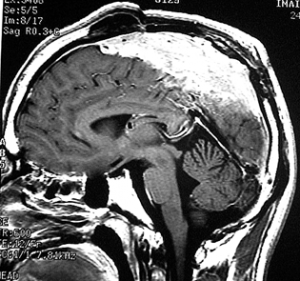

典型的な髄膜腫

この髄膜腫は中程度の大きさのものです。円蓋部髄膜種という最も多い最も手術の簡単なタイプです。麻痺や失語症やてんかんなどの症状はありません。とても美しくて若い女性の髄膜腫でしたが,子供に遺伝はしませんし,癌などと違ってタバコなどこれといった原因がなくて発生するものです。

MRIでの髄膜腫の見え方は撮影の仕方によっていろいろです。左からT1強調画像,T2強調画像,フレア画像といいます。腫瘍の横に小さく白い領域がありますが,これは脳の腫れた部分で脳浮腫といいます。髄膜腫があると周囲に脳浮腫が生じることがあります。

最も見やすいのが,ガドリニウム造影剤を注射して撮影するものです。一般的に髄膜腫は造影剤で白く映し出されます。この腫瘍は左脳側にあります。MRIの軸面という輪切りの写真では左右が逆になりますから注意してください。脳を下から見た図になっています。MRIはいろいろな方向から腫瘍を見ることができますが,右は冠状断という正面から見た図です。よく見ると腫瘍の上と下のはじっこに線状に糸を引いたように造影される部分があります。これをテールサイン(しっぽのサイン)といいます。腫瘍が硬膜に沿って延びている可能性があることを示しています。